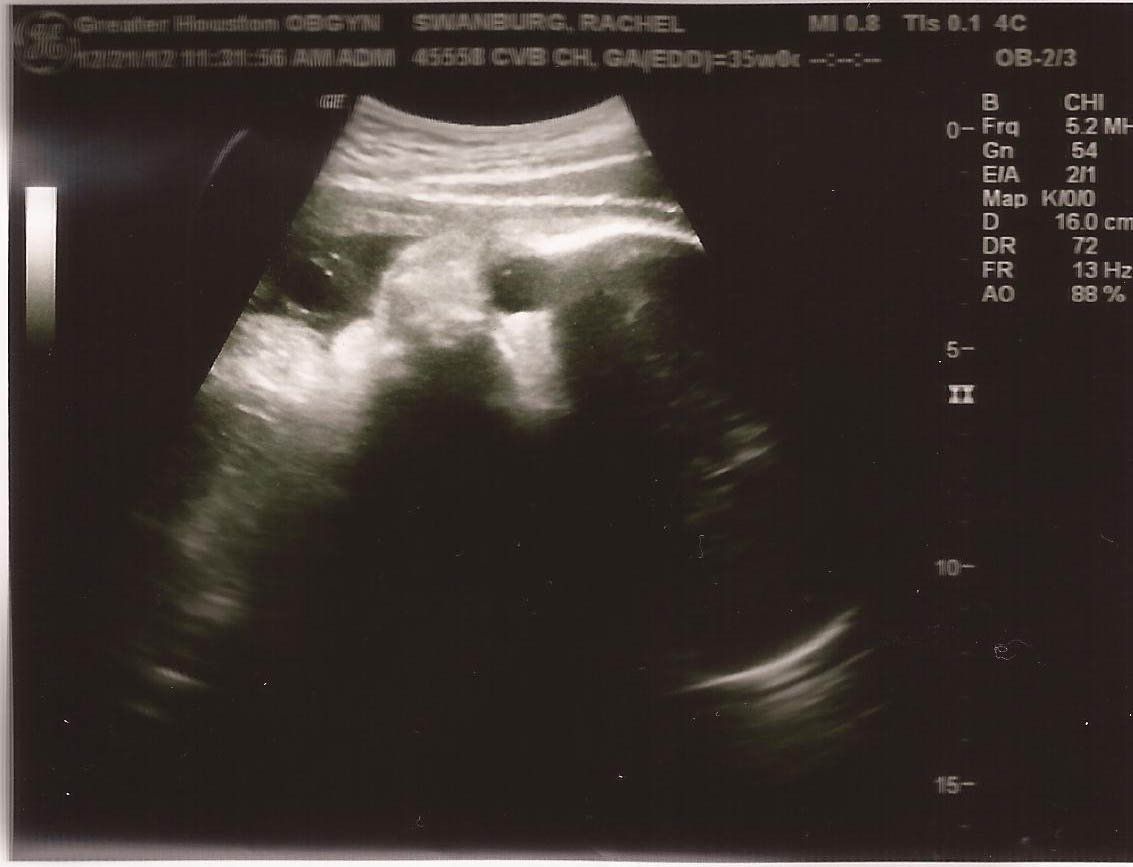

Liam's Final Prebirthday Picture

Friday was the last sonogram. The baby is currently a hairy 6lbs 8ozs and looks to be an amorphous space cloud.

This is something.

At the current stage babies grow at least a half pound a week.  If he makes it to January 21st, 4 weeks time, that would put him at 8lbs 8ozs.  The doctor thinks he may show up a little earlier.  Let’s hope he photographs better in color.